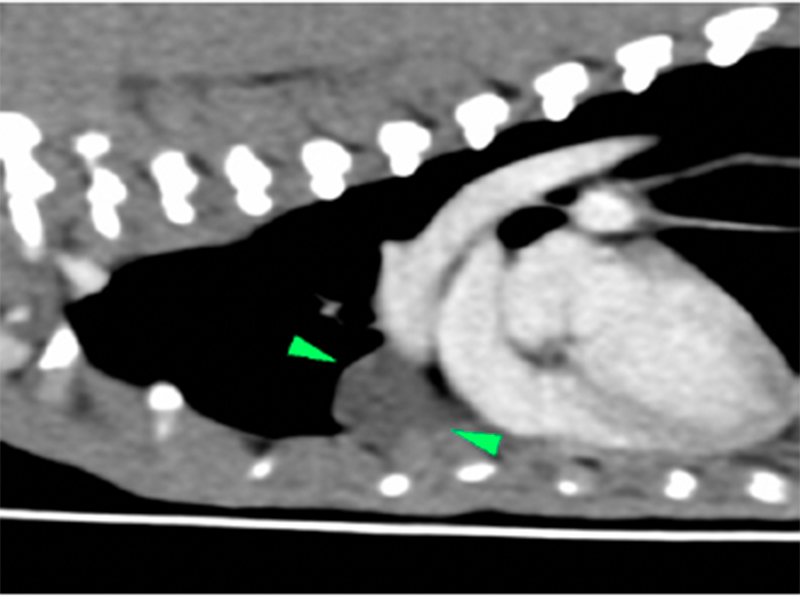

- Imaging: Film reading and more: imaging the thorax does not always have to be frustrating (TBC)